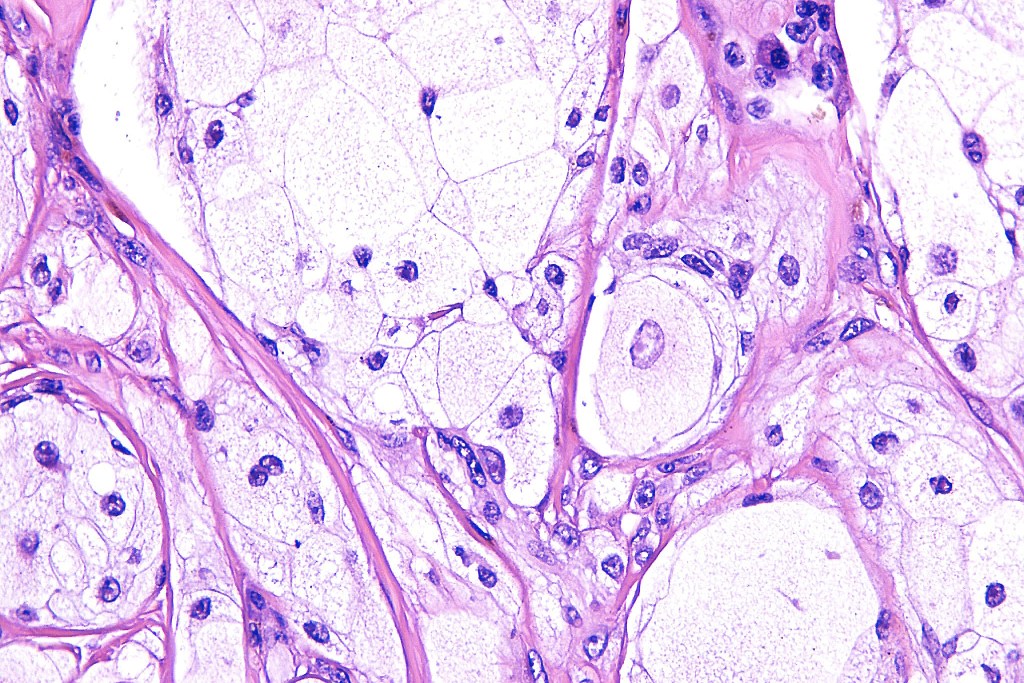

•Enlarged cells with copious eosinophilic, foamy or clear cytoplasm (some authors include melanoma with clear cell change in the same category)

•Variable pigmentation

•Nuclei vesicular or hyperchromatic

•Pleomorphism is not generally marked and indeed can be very subtle

•DPAS granules

•Thought to be a result of abnormal or degenerative melanosome change